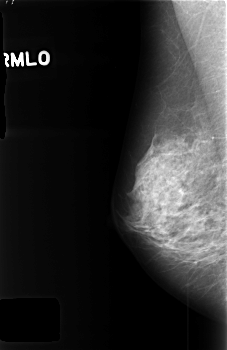

C_0426_1.RIGHT_MLO

RIGHT_MLO LINES 4544 PIXELS_PER_LINE 2944 BITS_PER_PIXEL 12 RESOLUTION 50 NON_OVERLAY